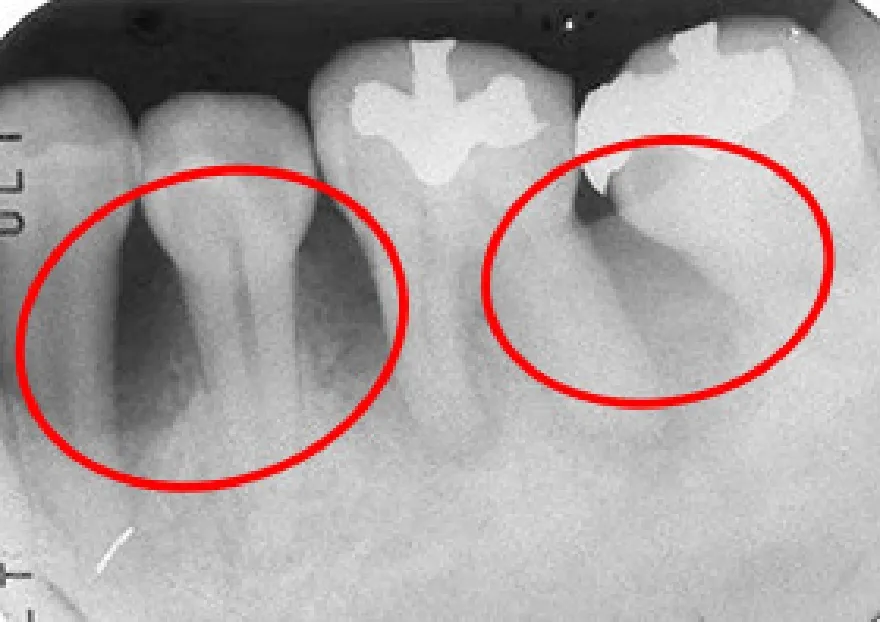

• 使用前のレントゲンです。根の周りが黒くなっているところが骨が溶けている所です。

• 使用後のレントゲンです。黒くなっていた部分に骨が出来て白くなっています。